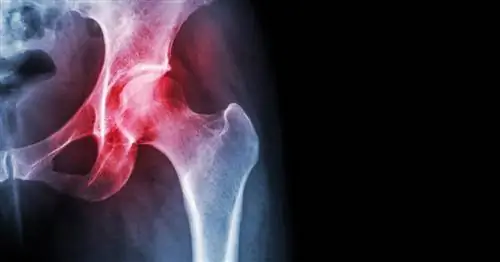

Искусственные тазобедренные суставы - очень хорошее решение, но, к сожалению, не навсегда. Хотя они изготовлены из таких прочных материалов, как керамика и титан, их недостаточно, чтобы прослужить всю жизнь, особенно если они имплантированы молодому человеку. Особенно хлопотно расшатывание частей, закрепленных в живой кости, которое может произойти через несколько лет. Причиной являются мягкие ткани, образующиеся вокруг металлических деталей. Стволовые клетки способствуют этому.

Ученые хотят покрыть важные поверхности протезов пластиковым нанорисунком, чтобы побуждать стволовые клетки формировать кость при контакте с новым суставом. Особый рисунок наноточек из полимера с сокращенным названием PEREK (полиарилэфиркетон) заставляет вокруг имплантата формироваться кость, а не мягкая ткань. Это снижает риск расшатывания.